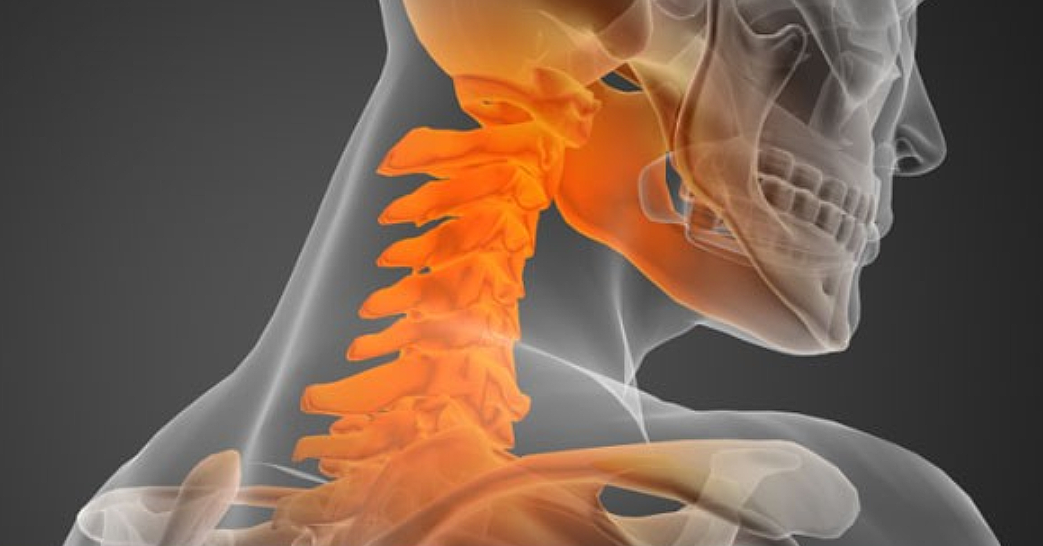

오늘 건강 정보는 목디스크 증상과 원인에 대해 알아보겠습니다. 엑스레이로 목을 촬영하면 목뼈가 c 곡선을 유지하는 것이 정상이라고 합니다. 하지만 요즘은 그렇지 않은 경우가 많은데요. 책상 앞에 앉아 있는 시간이 많기 때문에 머리를 숙이고 책을 보거나, 휴대 전화와 태블릿을 사용함으로써 잘못된 자세를 취하고 있기 때문에 목뼈의 배열이 흐트러지는 경우가 많습니다.

목을 받쳐주는 뼈를 경추라고 하는데 여기는 뼈가 7개 있고 이 뼈 마디마다 디스크라는것이 있습니다. 이 디스크의 역할은 척추 뼈 사이에 충격을 완화하고 운동할 수 있게합니다. 목디스크는 퇴행성 척추 질환으로 목 주위 근육, 인대가 장기간 압력을 받고 퇴행하여, 디스크가 자신의 역할을 하지 못하고 밀려나고 통증과 같은 목디스크 증상을 보이는 질병입니다. 이 디스크의 위치가 어디에 있는지에 따라 목 이외에도, 손이 저리거나 어깨가 아프고 두통과 같은 다른 목 디스크 증상을 일으킬 수 있습니다. 만약 여러분이 디스크를 그대로 방치하면, 몸이 마비되거나 호흡이 곤란한 상황에 처할 수 있기 때문에 여러분의 관심을 필요로 할 것입니다.